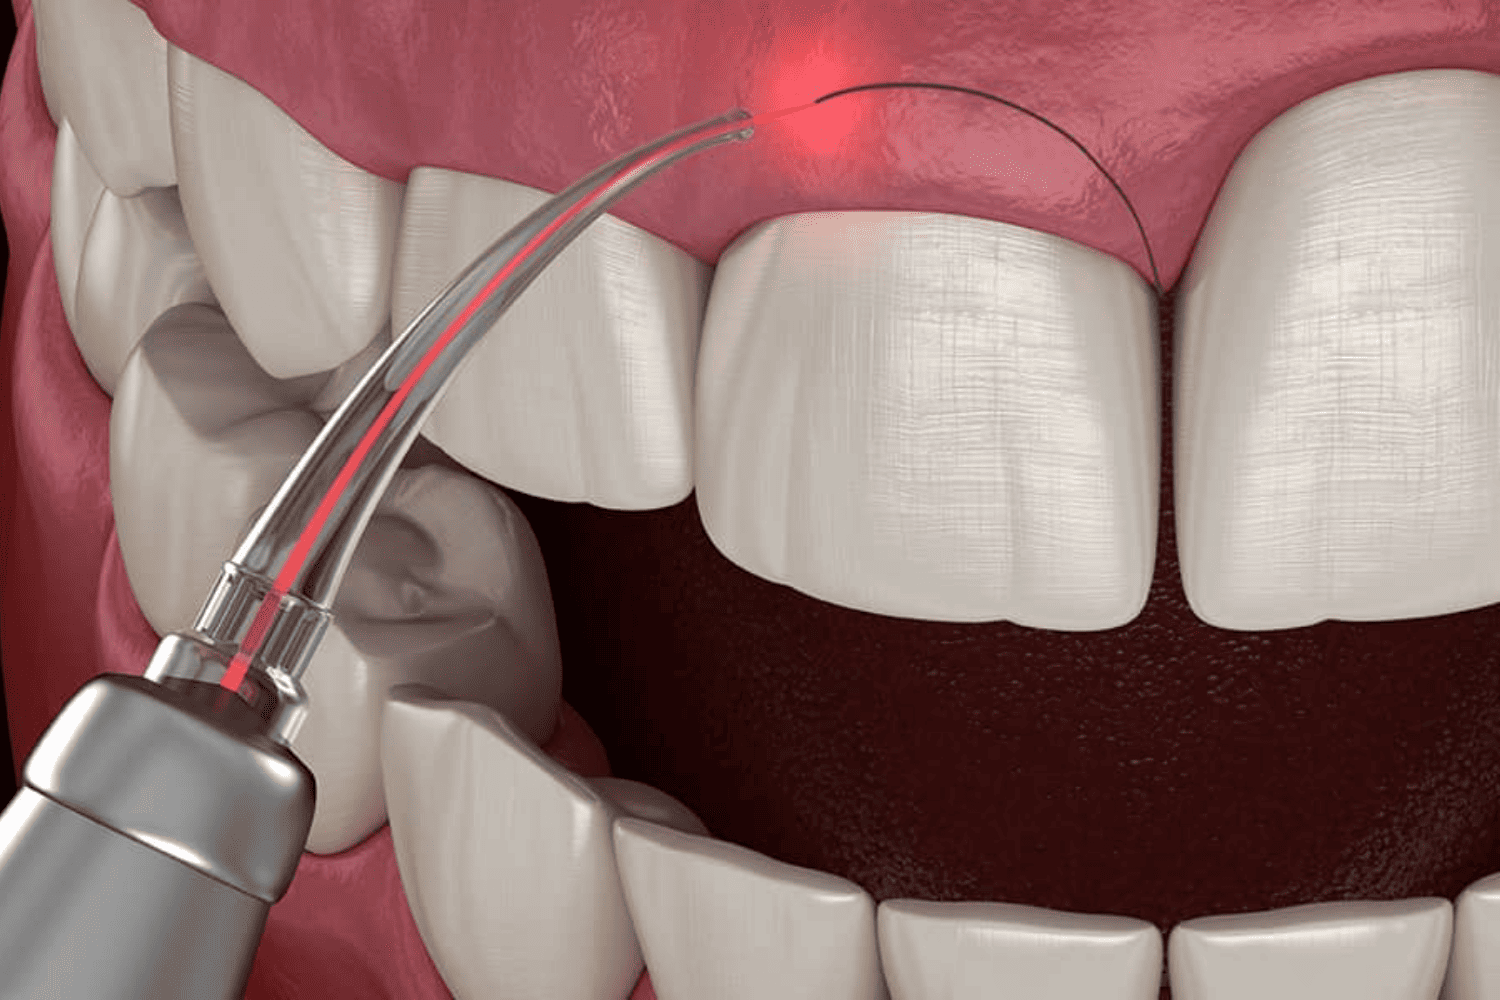

READ MORELaser Dentistry in Jaipur Services Crowns Bridges Dentures...